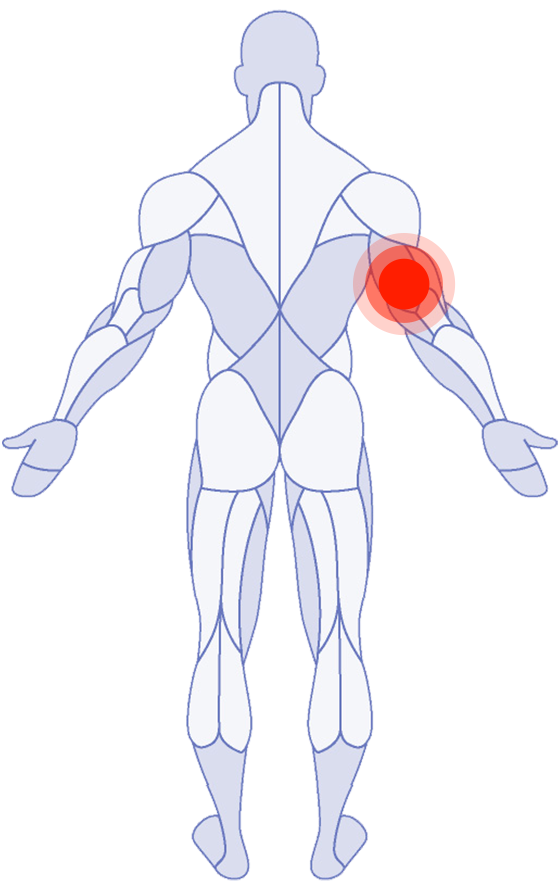

Where do you need attention?